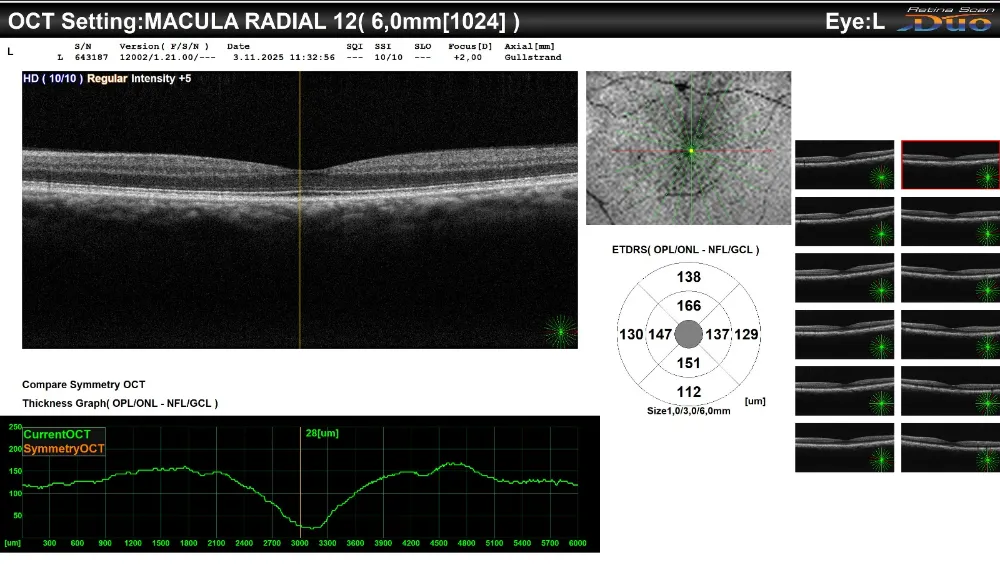

Gölcük Necati Çelik Devlet Hastanesi, göz sağlığı hizmetlerinde tanı ve takip süreçlerini güçlendirmek amacıyla Optik Koherens Tomografi (OCT) cihazını hizmete sundu. Yeni cihaz sayesinde retina, optik sinir, kornea ve ön segment yapıları mikron düzeyinde incelenebilecek; hastalara daha hızlı, güvenilir ve konforlu bir muayene deneyimi sağlanacak.

OCT teknolojisi, gözün hem arka (retina, makula, optik sinir başı) hem de ön segment (kornea, ön kamara) yapılarının temassız ve ağrısız şekilde görüntülenmesine olanak tanıyor.

Bu sayede glokom, diyabetik retinopati, makula dejenerasyonu gibi hastalıkların erken evrede tespiti mümkün hale gelirken, hastaların tedavi süreçleri daha etkin biçimde takip edilebilecek.

Yeni OCT cihazı, göz sağlığının pek çok alanında hizmet verecek:

• Retina hastalıklarının tanı ve takibi

• Glokom şüphesi ve glokom izleminde optik sinir lifi analizi

• Kornea ve ön segment değerlendirmeleri

• Göz cerrahisi sonrası kontroller